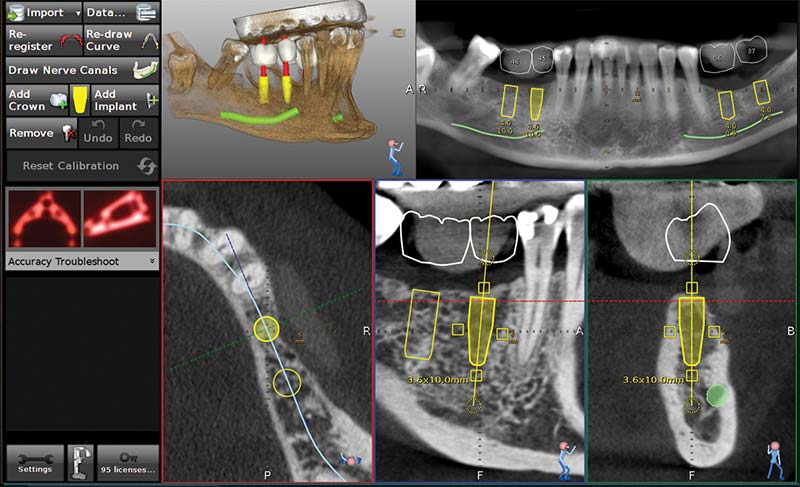

由AI模擬最佳治療方案

4D動態導航系統

手術實時顯影定位

「安適準(Navident)4D微創動態導航儀」搭載著新時代的黑科技,使用了以色列國 防黑科技的「超精準定位技術(Micron Tracker)」。透過安適準,醫師可以快速模擬 病患口腔狀況、運算治療方針,並運用AR擴增實境,在手術中實時顯示病患植牙狀況, AI會判讀最適合的植入位置,並隨時追蹤位置,發出警示,達到真正的微創植牙。

安適準導航植牙系統可以於植體製作前(術前)做第一次植牙流程規劃,判讀病患牙齒間狀況,並做出最合適的植牙療程建議。搭載高達12顆鏡頭,於手術間幾乎零死角定位植牙位置,配合AI高速運算,讓植體精準的植入齒骨,創造幾乎與原生牙齒無二的舒適感。

- 高達12顆鏡頭同步定位,視覺零死角

- AR實時成像,植入點寬度、深度毫釐不差

- 定位誤差小於0.2mm RMSE